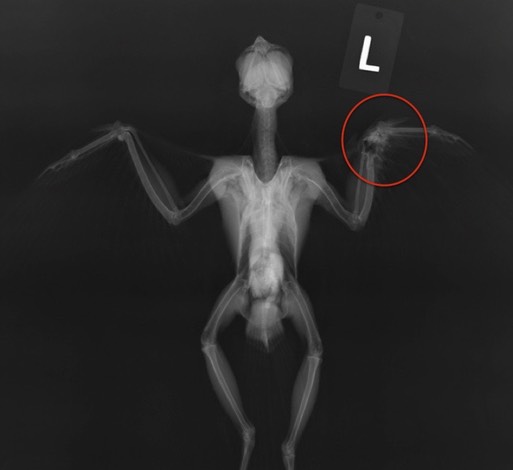

Bald Eagle 19-534, admitted two weeks ago with partially healed fractures in his left shoulder and left leg, is feeling much better. He’s been moved from a hospital cage outside to a mew where he can begin to exercise his shoulder and leg.

There were 8 new admissions this past week: 1 Merlin, 1 Sharp-shinned Hawk, 3 Red-tailed Hawks, 1 Western Screech Owl and 2 Great Horned Owls. We seem to be averaging two gunshot birds per week. This week it was the Merlin and Sharpie. The Sharp-shinned Hawk died of his injuries, scapula and leg fractures, a few hours after admission. The Merlin’s injuries were not repairable and she was euthanized.